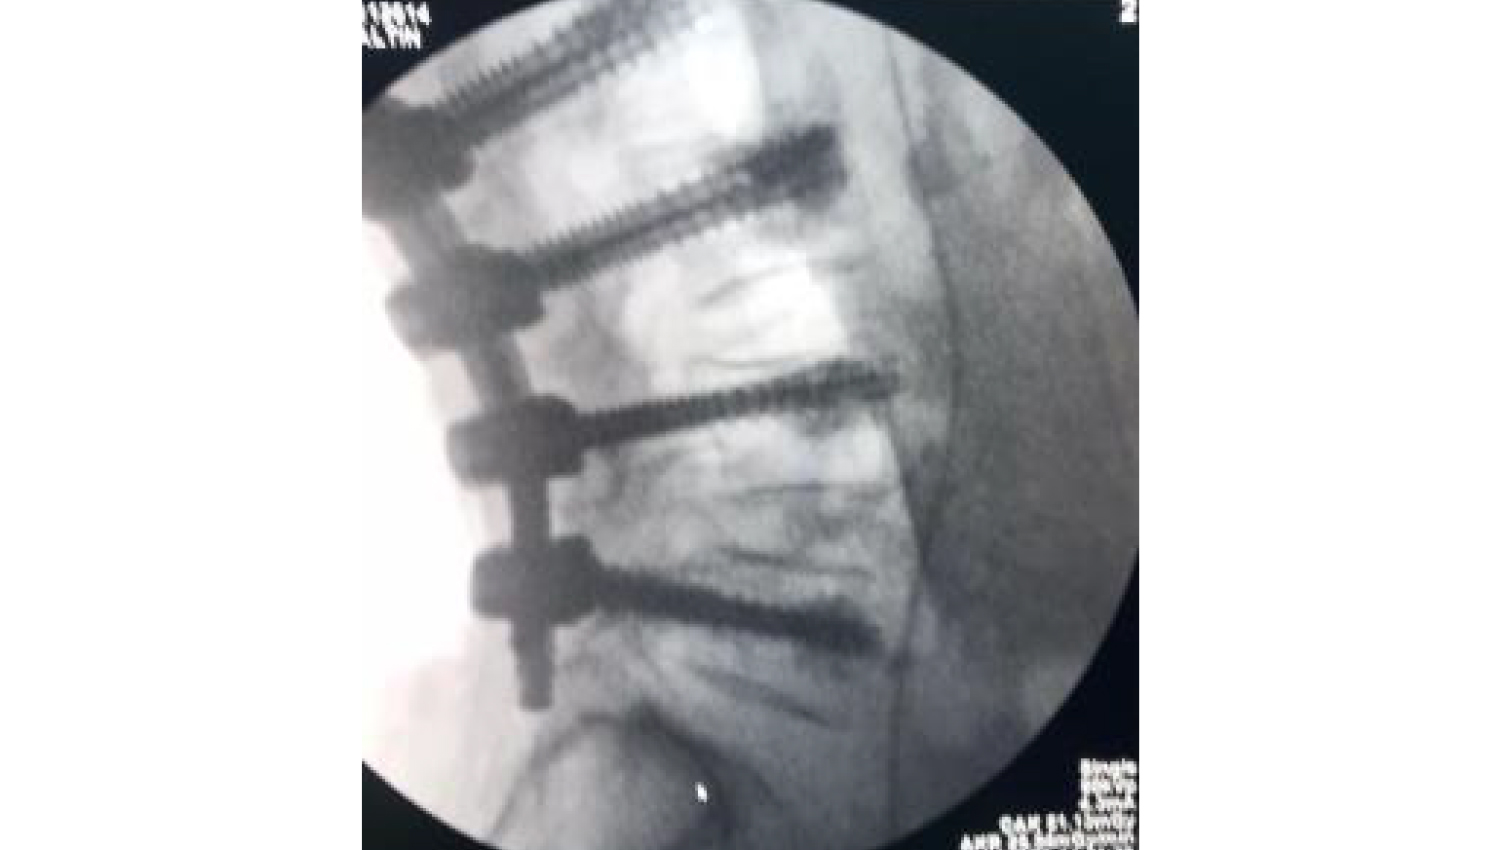

6.Final radiological view.